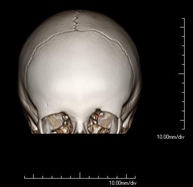

- Neuroradiology

- Skull CT

Radiological test that provides high definition anatomical images of the skull (brain stem, cerebellum, cerebrum, cranial calotte, etc.) using CT (Computed Tomography) equipment. Indicated for: trauma, headache, memory disorders, sudden loss of strength in a limb or half of the body.